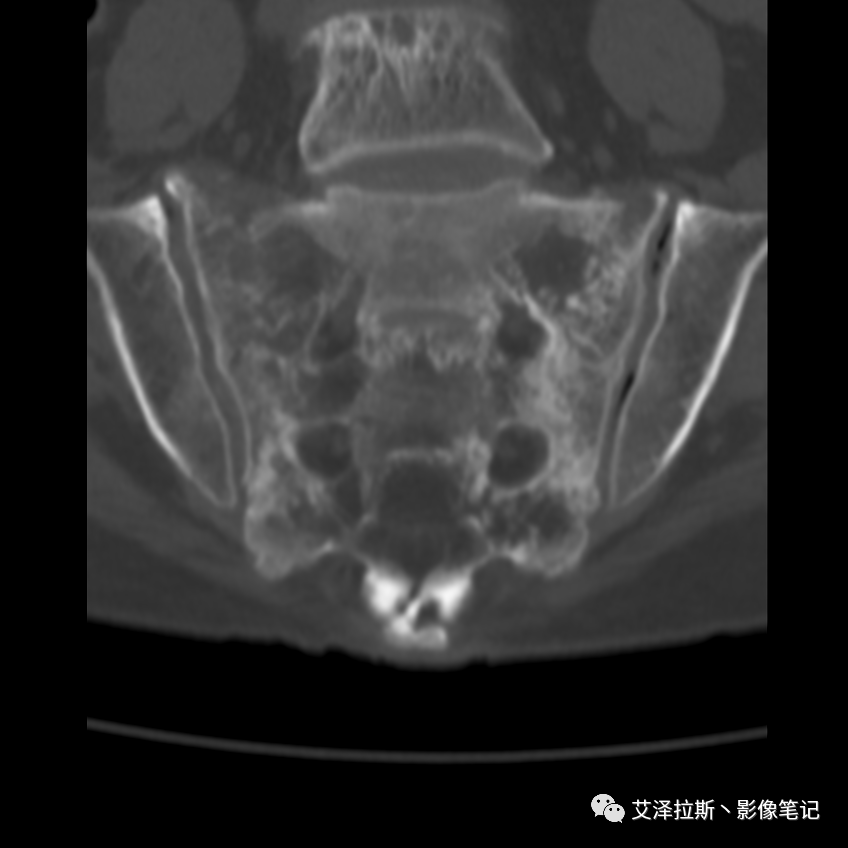

病例1:患者,女性,88岁,重度骨质疏松。

病例1

CT平扫:

影像所见

X线、CT:骶骨重度骨质疏松,双侧骶骨翼皮质断裂,分别见迂曲走行的纵行透亮线位于骶孔外侧,大致与骶髂关节间隙平行,骨折端局部可见骨痂、骨质硬化。

诊断意见

骶骨功能不全骨折